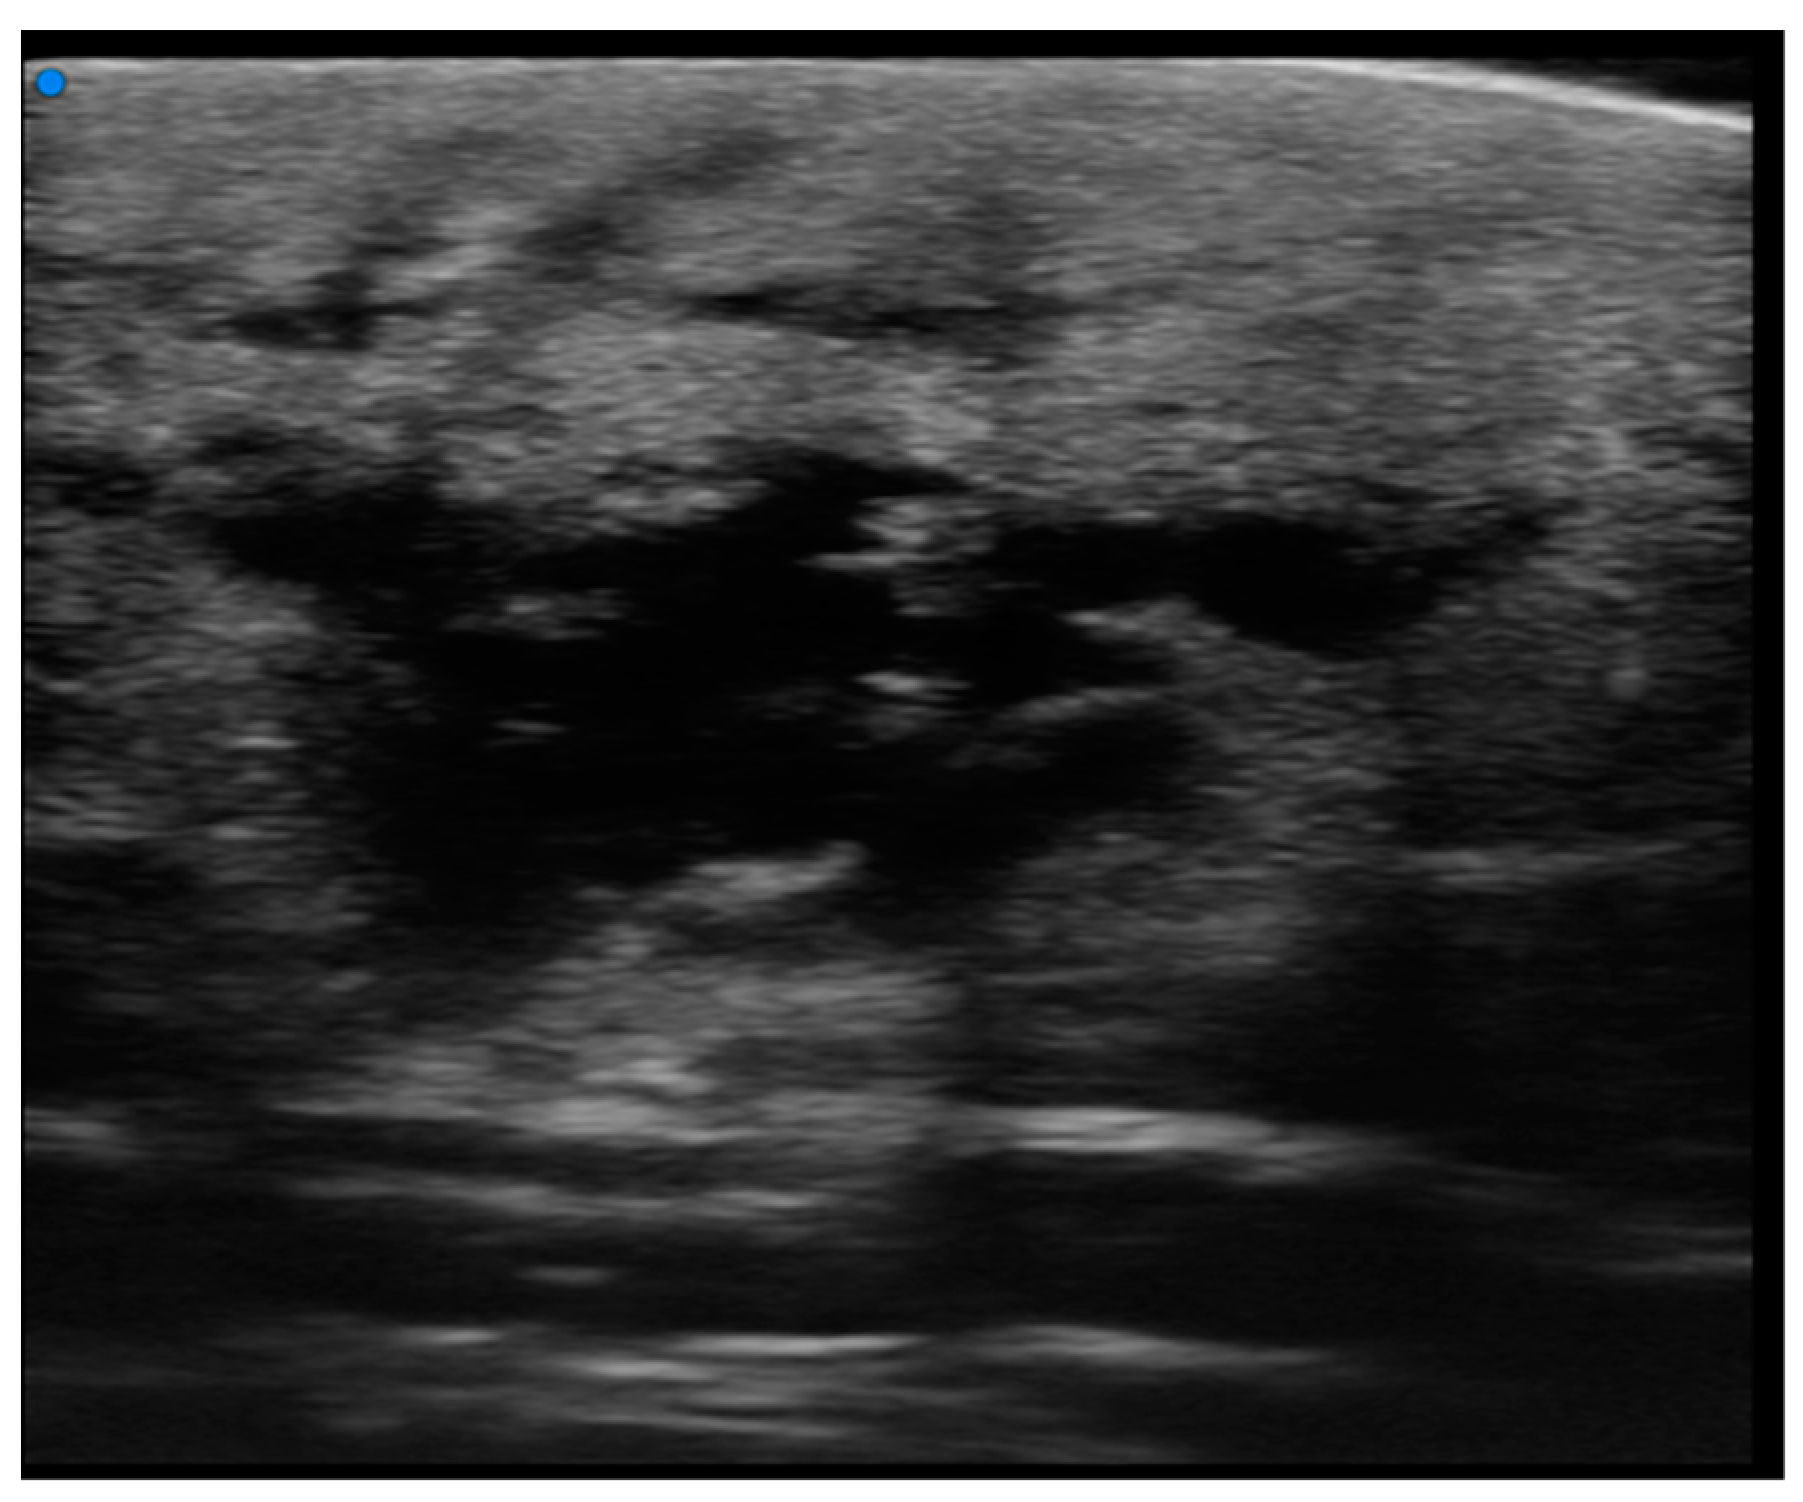

Single or multiple hypoechoic nodules (Figure 2) with focal epidermal–subepidermal involvement, featuring regular margins without peripheral infiltration, were typical of B-cell lymphoma (Figure 3 and Figure 4).

Figure 2. HFUS assessment of a round hypoechoic subepidermal nodular lesion showing no infiltration of deeper planes. Pathological assessment revealed it to be a B cell Primary Cutaneous Lymphoma.